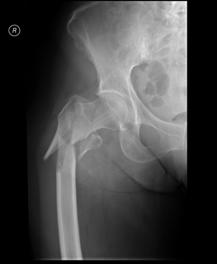

Luxatie de sold stang Luxatie de sold stang

Fractura

de cap femural Fractura de cap femural

Aspect

CT

de cap femural Fractura subcapitala cu usoara deplasare

Aspect CT

Fractura intertrohanteriana multifragmentara Luxatie de patela